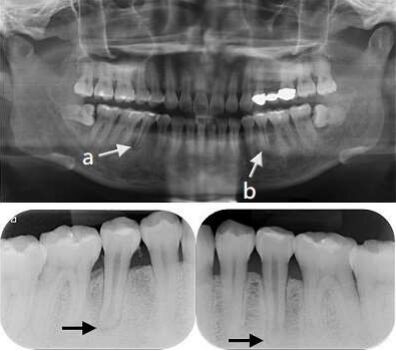

69.38歲女性,主訴右側牙齦持續腫脹、咬痛數週,口檢時發現右下第二小臼齒頰側黏膜牙齦連接 (mucogingival junction)附近有膿腫(abscess),電髓試驗結果10/10。環口放射線攝影 (panoramic radiography)與牙根尖放射線攝影(periapical radiography)結果如附圖。有關 箭頭所標示的放射線透過性(radiolucent)區域,下列敘述何者正確?(A)a是根尖炎性疾病(periapical inflammatory disease)造成的;b是頦孔(mental foramen)(B)a與b都是根尖炎性疾病(periapical inflammatory disease)造成的(C)a是頦孔(mental foramen);b是根尖炎性疾病(periapical inflammatory disease)造成的(D)a與b都是頦孔(mental foramen)